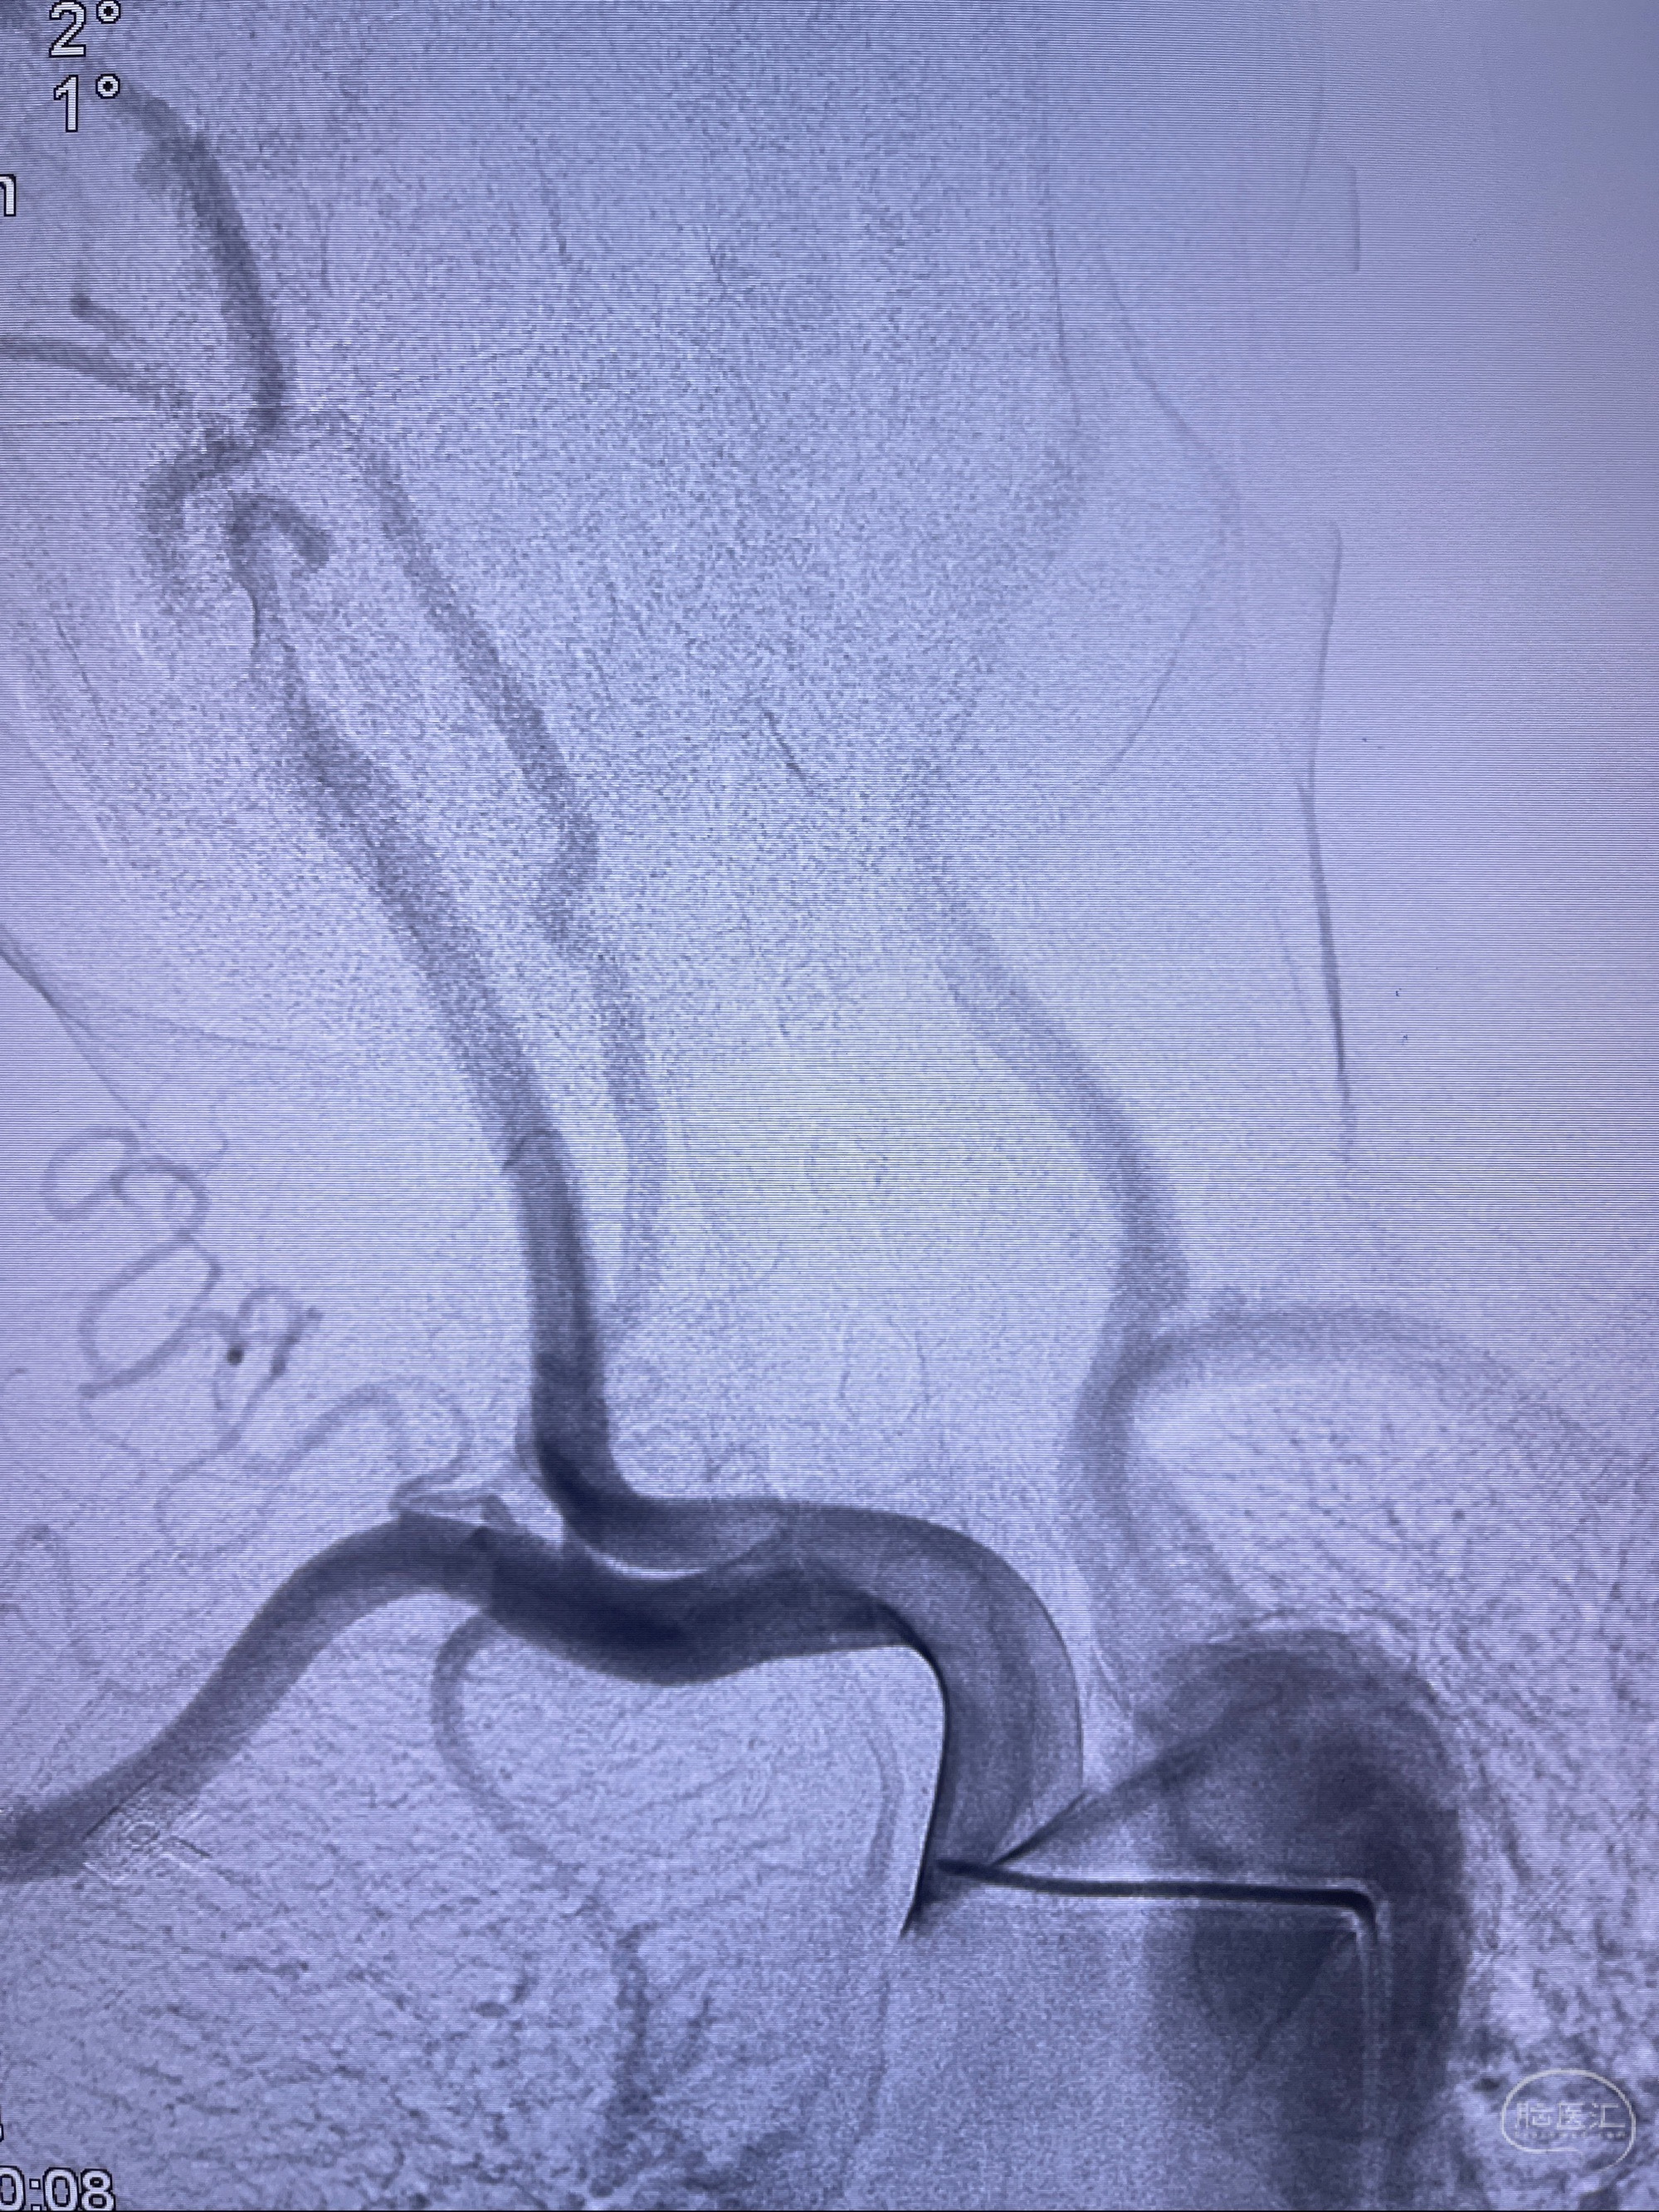

检查;2023-7-18 抚州市第一人民医院 头颈部CTA:左侧大脑前动脉A2段动脉瘤,左侧颈内动脉C4段轻度狭窄,右侧颈内动脉C6段中度狭窄

2023-08-23DSA:左侧前交通动脉瘤,左侧A3/4交界处多发动脉瘤